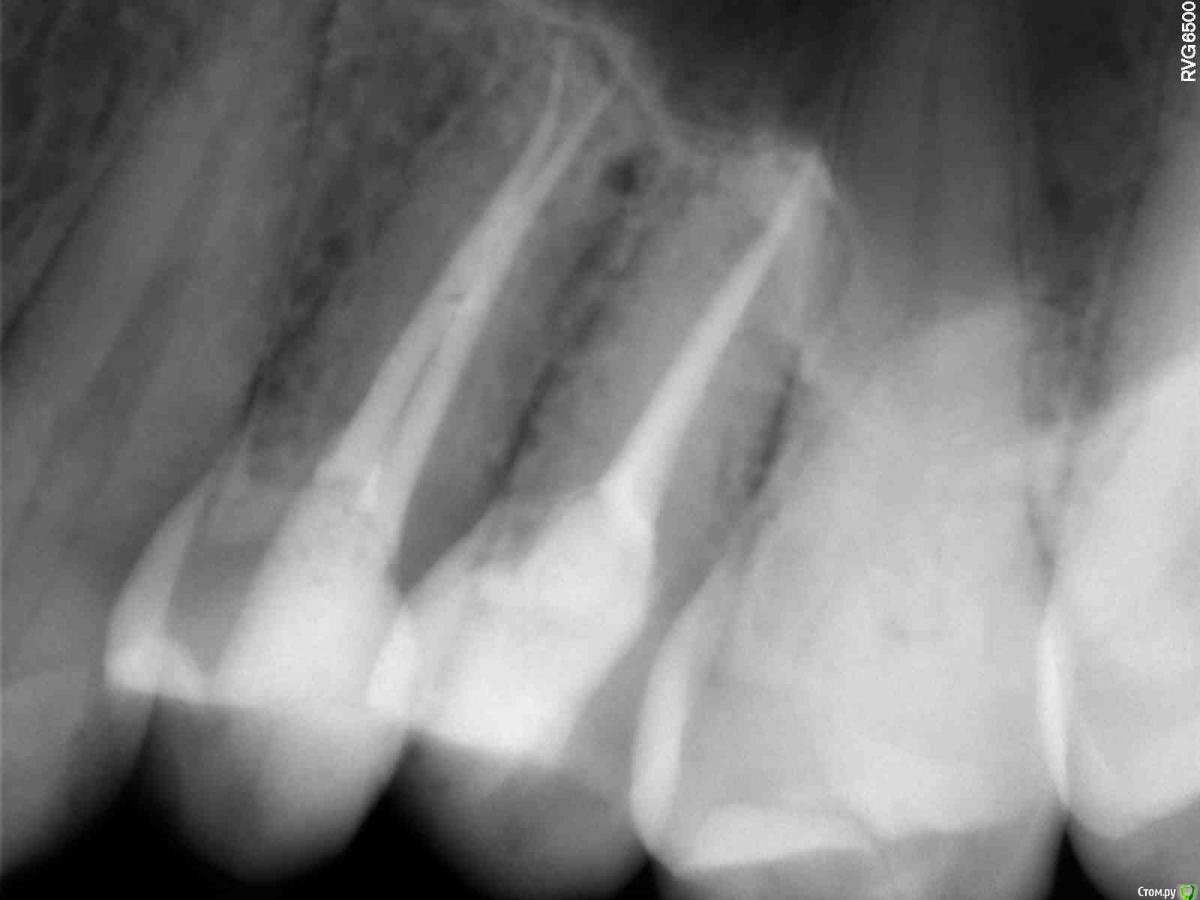

Алина08 Опубликовано 7 ноября, 2020 Поделиться Опубликовано 7 ноября, 2020 Добавлю ещё в эту тему. Здравствуйте, дорогие доктора, помогите пожалуйста,прилагаю панорам снимок. Слева были в феврале удалены мудрости, сверху вырезано,снизу вырван.Удаления были не сложные, но постоянно что-то мешало мне в ухе, а сейчас так вобще больно нажимать на челюсть снизу, болит челюсть, где 7 зуб и до подбородка. На кт было очень похоже на остаток корня рядом с корнем 7 зуба , но потом сказали это цвет кости такой другой. Сделала панораму и по мне так снизу явно видно, что там что-то есть. Как думаете? И что сверху слева у корня 7 зуба рядом?Мучают и боли лица, область пазухи и до глаза, там зубы 4 перелечили, 5 вывели материал сильно за корень , перелечили мта. Сейчас с 6 зуба достают пломбировочный материал, имеется аллергия на никель, в гутаперчи есть оксид никеля.Всё под микроскопом делалось, претензий к зубам нет у врачей, а боли начались как вскрыли 5 зуб, потом перелечили 4,не прошло, было ощущение распирания зубов, вскрыли 6 там дентикль, теперь его перелечивают, исключая аллерген контакт со слизистой, имею большие пазухи . Боль постоянная, распирающая, чувство давления на зубы. Может ли это боль снизу идти наверх? Выпито куча таблеток от невралгии, не помогает. Предлагают рвк 5 зуба, так как он на стук и кушать самый больной, у 6 зуба, если материал весь не достанут, осталось пару мм, тоже один корень верхушку убрать, но там пазуха рядом, не факт, что врач возмется. Придагалаю панораму и маленькие снимки 4,5,6 зубов.Больше меня сейчас волнует, есть ли кусок корня снизу от 8 зуба. Ссылка на комментарий

сирена Опубликовано 8 ноября, 2020 Поделиться Опубликовано 8 ноября, 2020 Компьютерную томограмму в идеале бы сделать,на прицельном снимке не совсем понятно,что у Вас там с пятым зубом.Если мышцы проверяли,то мфс исключаем.Это предположение было,я же не видела Вас вживую и не знаю,как Вас обследовали. Ссылка на комментарий

Алина08 Опубликовано 8 ноября, 2020 Автор Поделиться Опубликовано 8 ноября, 2020 Компьютерную томограмму в идеале бы сделать,на прицельном снимке не совсем понятно,что у Вас там с пятым зубом.Если мышцы проверяли,то мфс исключаем.Это предположение было,я же не видела Вас вживую и не знаю,как Вас обследовали.Боль в мышце действительно бывает после долгого открытия рта, но потом проходит, а основные боли остаются. Кт есть, мне не залить сюда, новый даже не открывается на компе дома, но там особо ничего не видят, кроме утолщения слизистой пазухи и вот вчера, над корнем слева показали что-то есть, похоже на гранулему 2 мм, но зуб уже забит мта качественно, а до этого гутаперча выведена за верхушку была, а гранулема, слева от верхушки, прям под костной слизистой пазухи. Что-то ведь вызыает его подвижность. Врачи до сих пор сомневаются, что если я его вырву, все пройдёт. А рвк на подвижный зуб как то страшно, к тому же на зуб надо коронку, разрушена стенка. К вечеру смогу показать только кт зуба до начало корневого лечения, может там что видно будет. 4 и 5 зуб под коронки и из за болей 8 месяцев не могу их поставить, зубы с прикуса выведены почти Ссылка на комментарий